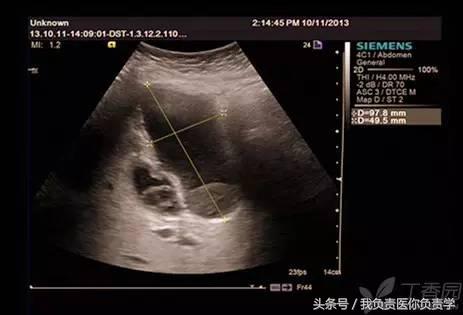

图1示胆囊体积明显增大,内部透声差

图2示胆囊周围可见液性暗区分布